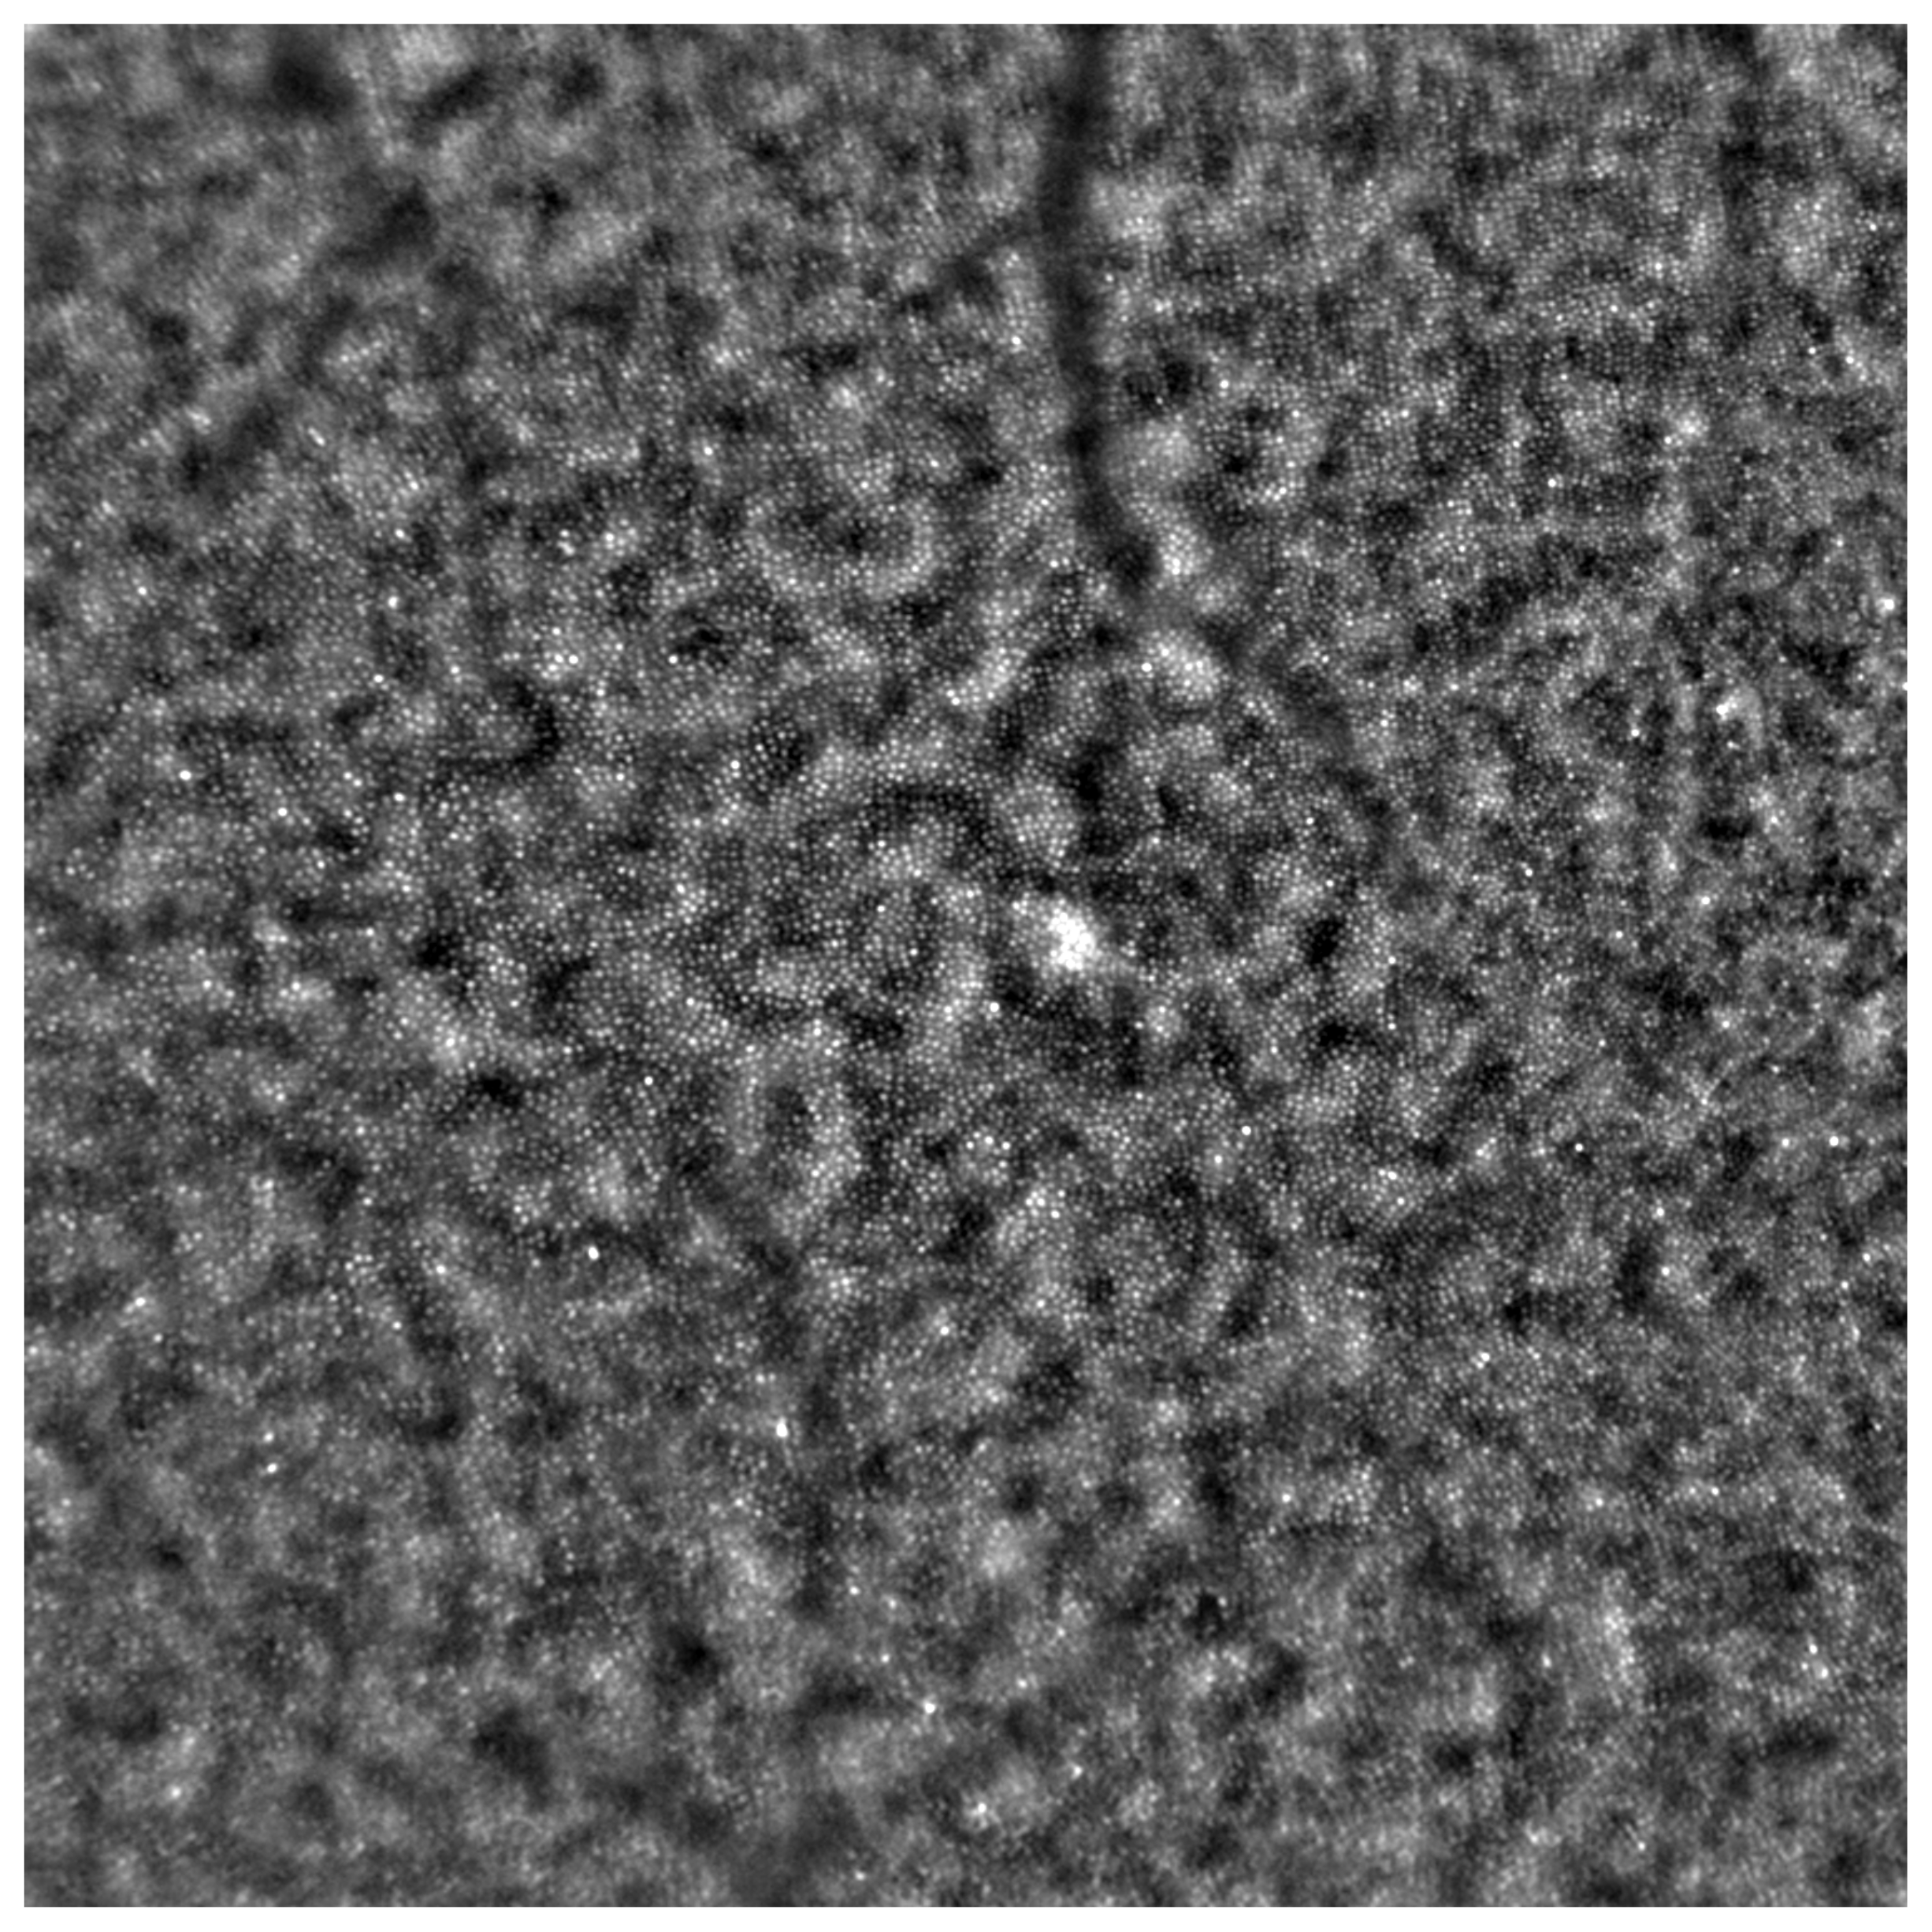

- Samelska, K.; Kupis, M.; Zaleska-Żmijewska, A.; Szaflik, J.P. Adaptive optics imaging in the most common inherited retinal degenerations. Klin. Ocz. 2021, 123, 74–79. [Google Scholar] [CrossRef]

- Gill, J.S.; Moosajee, M.; Dubis, A.M. Cellular imaging of inherited retinal diseases using adaptive optics. Eye 2019, 33, 1683–1698. [Google Scholar] [CrossRef]

- Zaleska-Żmijewska, A.; Wawrzyniak, Z.M.; Ulińska, M.; Szaflik, J.; Dąbrowska, A.; Szaflik, J.P. Human photoreceptor cone density measured with adaptive optics technology (rtx1 device) in healthy eyes: Standardization of measurements. Medicine 2017, 96, e7300. [Google Scholar] [CrossRef]

- Zaleska-Żmijewska, A.; Wawrzyniak, Z.M.; Dąbrowska, A.; Szaflik, J.P. Adaptive Optics (rtx1) High-Resolution Imaging of Photoreceptors and Retinal Arteries in Patients with Diabetic Retinopathy. J. Diabetes Res. 2019, 2019, 9548324. [Google Scholar] [CrossRef]